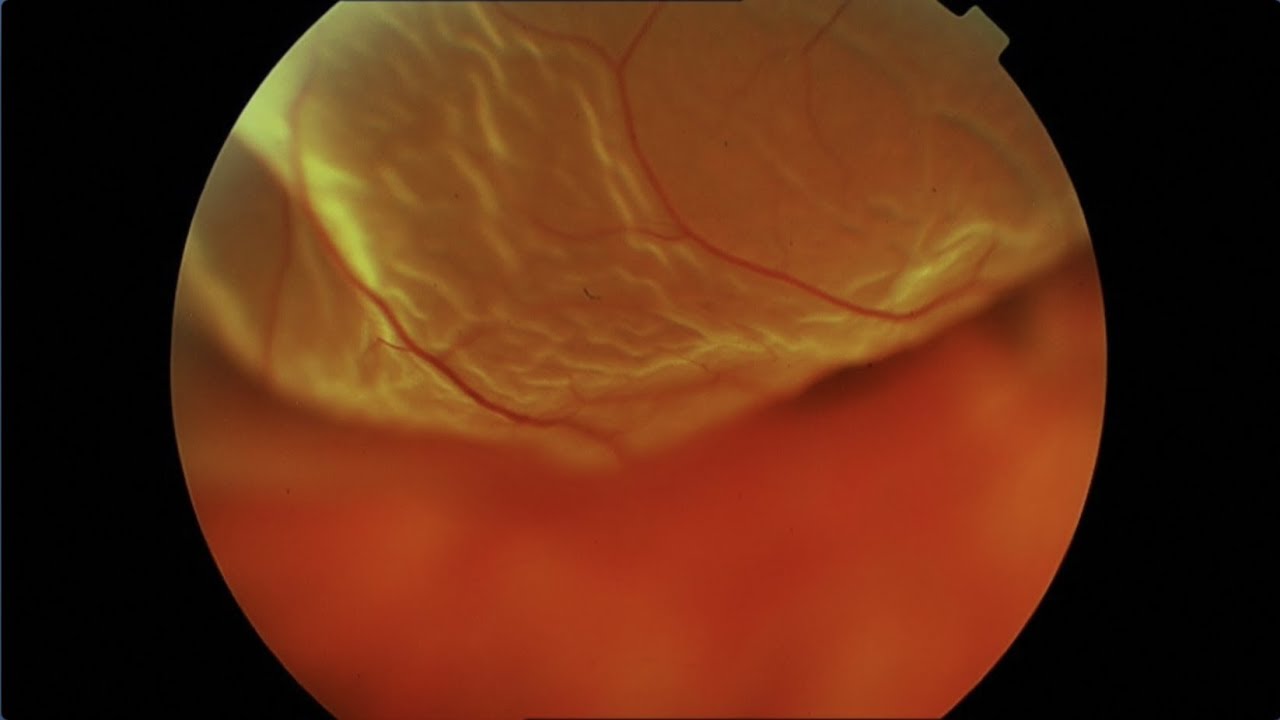

HELIOS   ophtalmologie   Dr SOYEUR   DECOLLEMENT DE RETINE

Les centres ophtamologiques Hélios à Saint Jean de Luz et Activa à Pau propose : Dr SOYEUR DECOLLEMENT DE RETINE